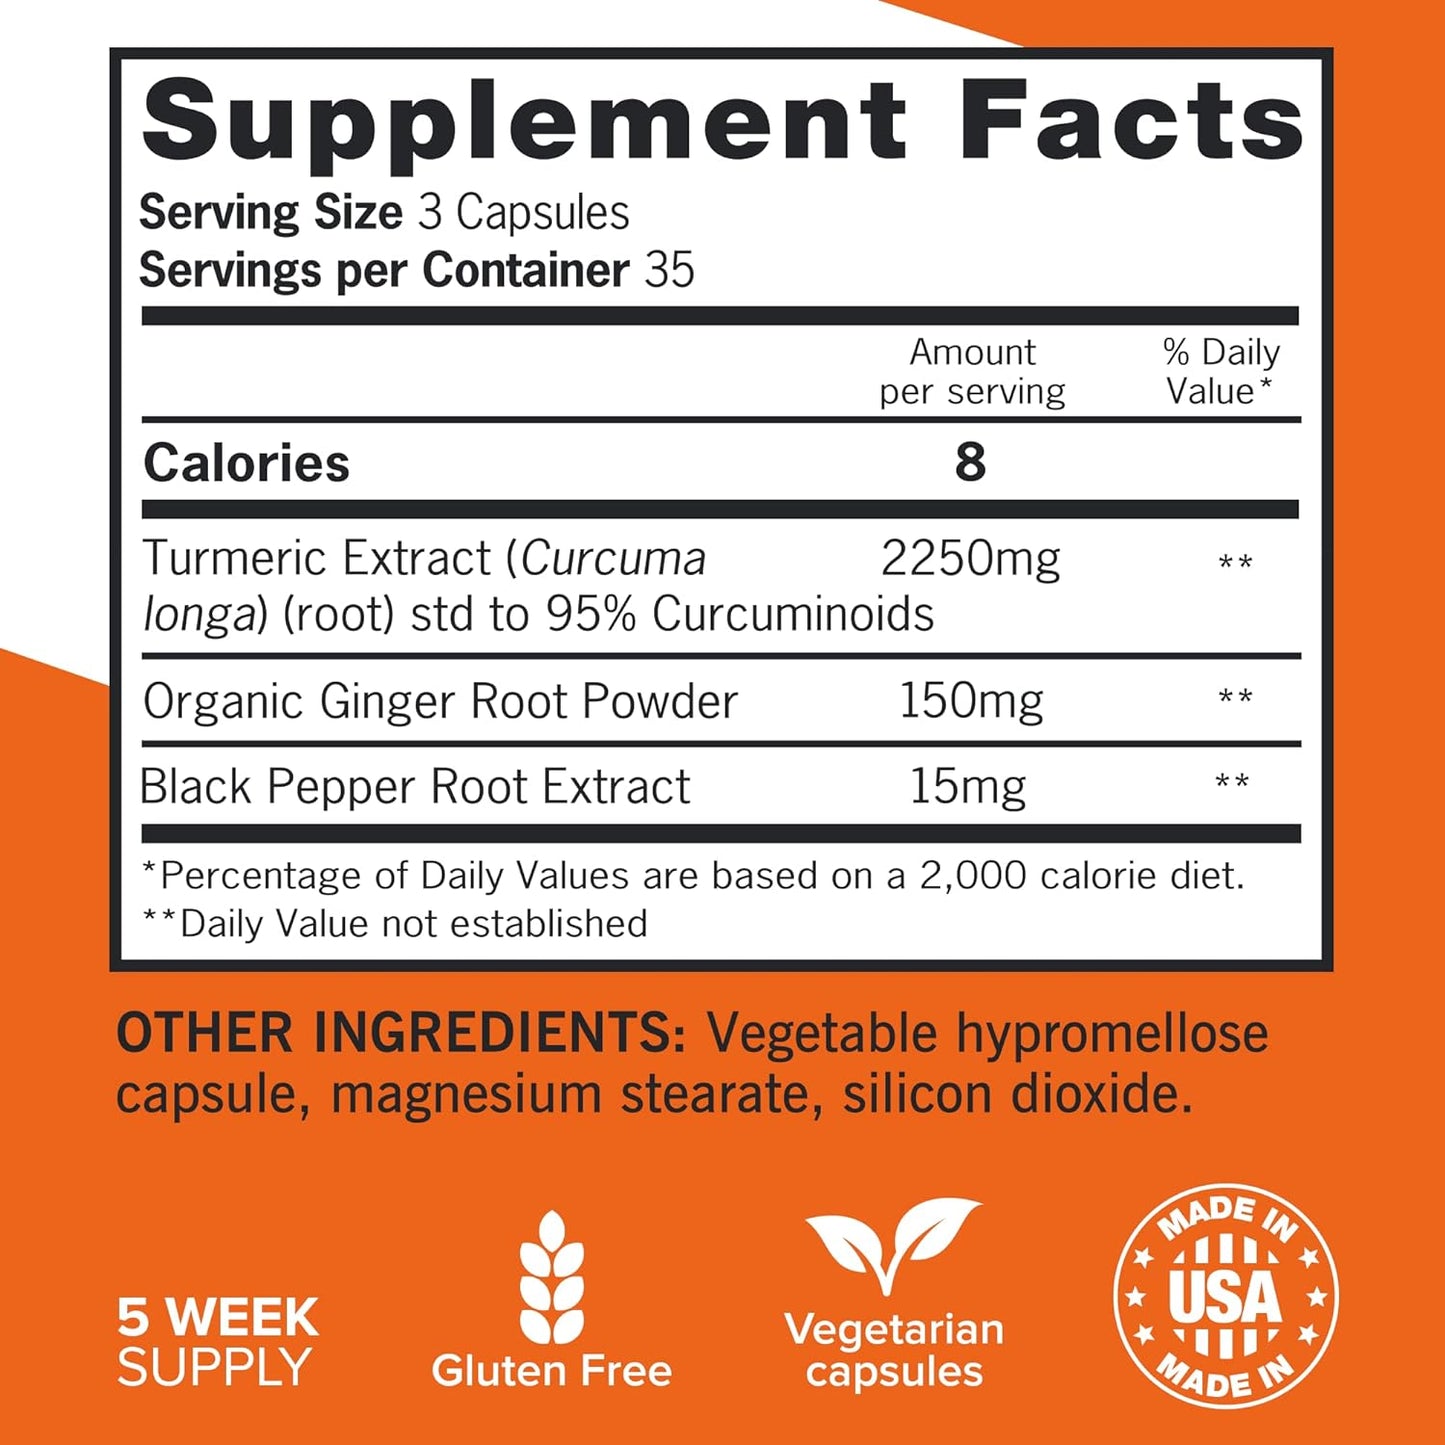

Unlock your potential with this powerful blend of turmeric, black pepper, and ginger, designed to support joint health and enhance your active lifestyle. Embrace vitality and comfort every day with our extra-strength formula.

- 2400mg turmeric extract per serving

- 95% curcuminoids for maximum benefits

- Enhanced absorption with black pepper

- Organic ginger root for soothing support

Question 3: Is this supplement safe for daily use, and are there any specific dietary considerations?

Answer 3: Yes, this supplement is made with natural, clean ingredients and is designed for daily use. However, it’s advisable to consult with a healthcare professional if you have any underlying health conditions or are taking medications, especially since ginger may have blood-thinning properties.